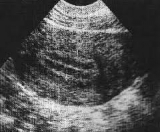

Endometrio de 5 mm este año

Uno de las posibles complicaciones de un legrado es el llamado Sd de Asherman en el cual se producen adhrencias a nivel úterino dificultado el crecimiento del endometrio durante el ciclo menstrual de la mujer. Si este es el caso se puede intentar liberar las adherencias mediante histeroscopia. Sin embargo por lo que me explicas si llegaron a tener un endometrio de 5 mm debería ser suficiente para conseguir un embarazo si bien es verdad que lo deseable es algo más grueso.